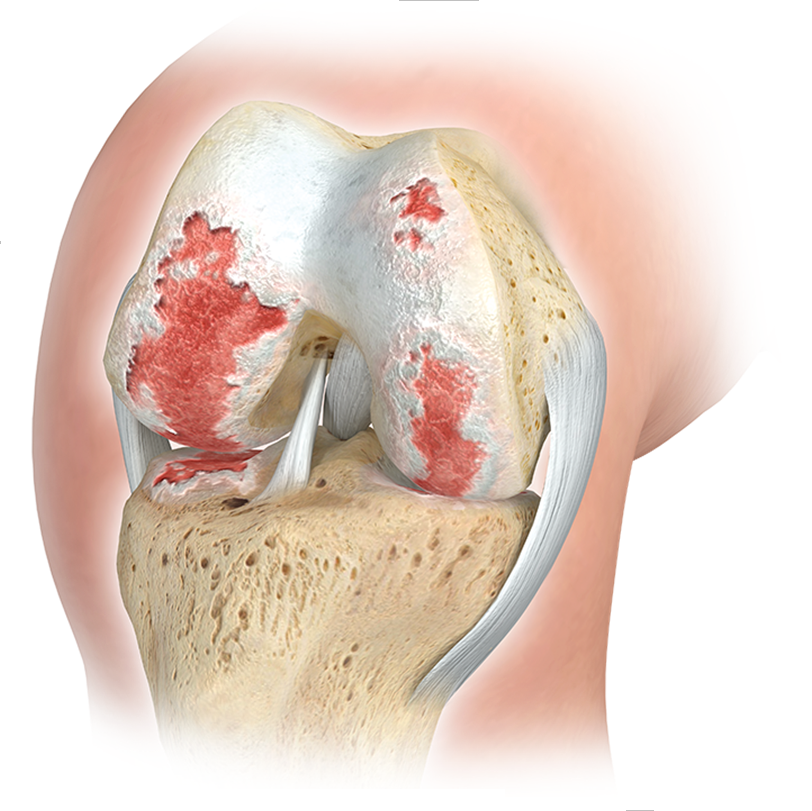

EN RAISON du niveau de stress élevé auquel les articulations du genou sont exposées, des signes d'usure apparaissent souvent au cours de la vie, entraînant un inconfort important et des restrictions sur la qualité de vie. Les blessures sportives précoces, les désalignements ou l’obésité favorisent considérablement cette évolution.

DANS LE CADRE DU THÉRAPIE DE L'ARTHROSE DU GENOU (arthrose du genou), DES INTERVENTIONS CHIRURGICALES PEUVENT ÉGALEMENT ÊTRE NÉCESSAIRES EN PLUS DES MESURES CONSERVATIVES :

- OPÉRATIONS DE PRÉSERVATION DES ARTICULATIONS DE L'ARTICULATION DU GENOU (CORRECTION DE POSITIONS DIVERSES ET DE VARIANTES ANATOMIQUES PAR MIRROROSCRIPTION ARTICULAIRE MINI-INVASIVE (ARTHROSCOPIE), PARFOIS ÉGALEMENT PAR OUVERTURE ARTICULAIRE (MINI-OPEN). OPÉRATIONS ENDOPROTHÉTIQUES DE L'ARTICULATION DU GENOU (REMPLACEMENT DES PARTIES ARTICULAIRES DÉTRUITES PAR IMPLANTS ARTIFICIELS EN MÉTAL ET PLASTIQUE HAUTEMENT RÉTICULÉ) .